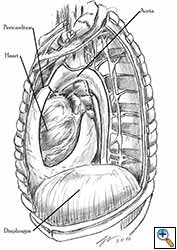

Medium and large-sized (Figures 1a, 1b) defects generally result after pneumonectomy for advanced central lung tumours which invade the pericardium (T3 invading pericardium), thus requiring reconstruction (Figure 1c). To achieve a curative resection, negative pericardial resection margins must be obtained and checked microscopically. More invasive tumours (T4 invading cardiac structures) require partial atrial resection and pericardiectomy associated with pneumonectomy.

|

| Figure 1c: Intraoperative aspect of pericardioplasty with Marlex mesh after right completion pneumonectomy with partial pericardiectomy. |

Video 1 depicts a pericardial reconstruction with Marlex after a right completion pneumonectomy with pericardiectomy for lung adenocarcinoma (see also Figure 1). The technique of pericardial reconstruction after the resection of invasive mediastinal tumours is illustrated in Figures 8a-c). Video 2 depicts a pericardial reconstruction with Mersilene mesh after the resection of a malignant thymoma invading the anterior pericardium (see also Figure 4b). The technique of right pericardial reconstruction after extrapleural pneumonectomy is illustrated in Figures 9a and 9b). Video 3 depicts a pericardial reconstruction using Gore-Tex Dual Mesh after a left extrapleural pneumonectomy (see also Figure 3). Care must be taken to prevent constriction (Figure 10).